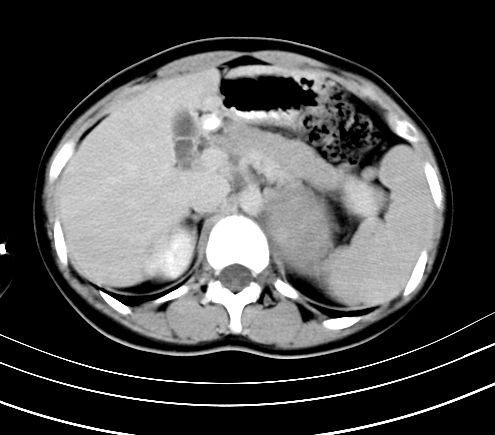

腹部平扫